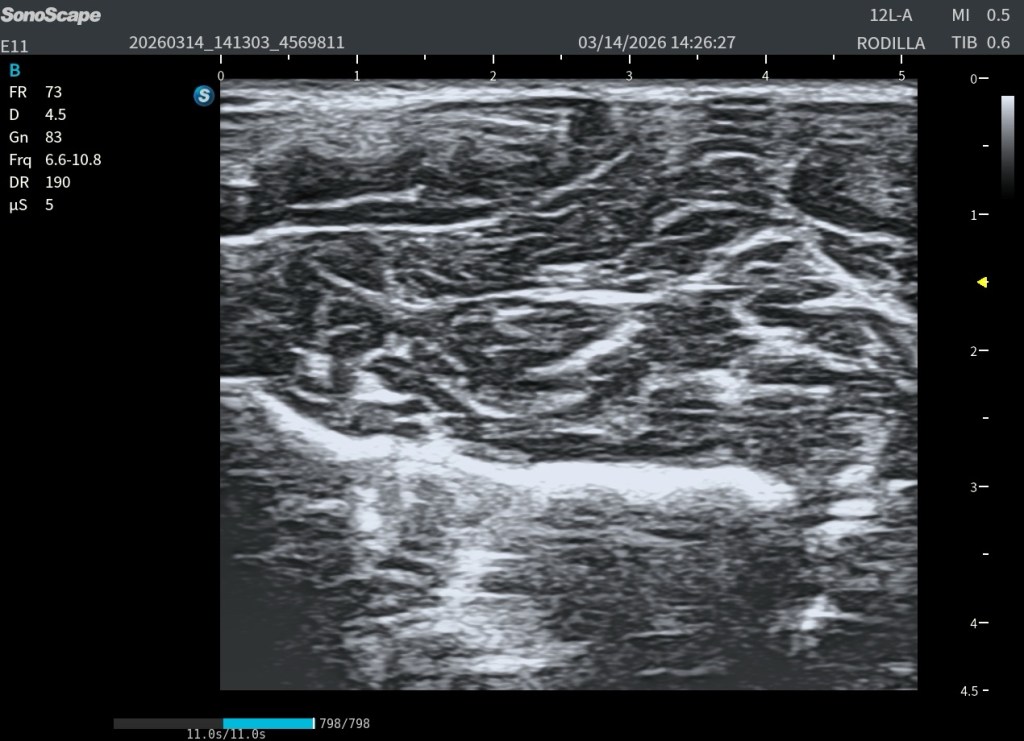

Si utilizamos una frecuencia muy alta, por ejemplo 18 MHz, la resolución en las capas superficiales será excelente. Pero si el músculo es grande o el paciente tiene bastante tejido subcutáneo, el ultrasonido se atenúa mucho antes de llegar a las fibras profundas.

En esa situación llegará menos energía al fondo del músculo y los ecos que regresan serán más débiles. La zona profunda aparecerá más oscura y la relación señal-ruido empeorará.

Si en esa misma exploración bajamos la frecuencia a 10–12 MHz, la penetración del ultrasonido mejora. Los ecos de las fibras musculares profundas regresan con mayor amplitud y la imagen se vuelve más homogénea. Aunque la resolución absoluta sea ligeramente menor, la calidad global de la imagen mejora porque la relación señal-ruido es mejor.